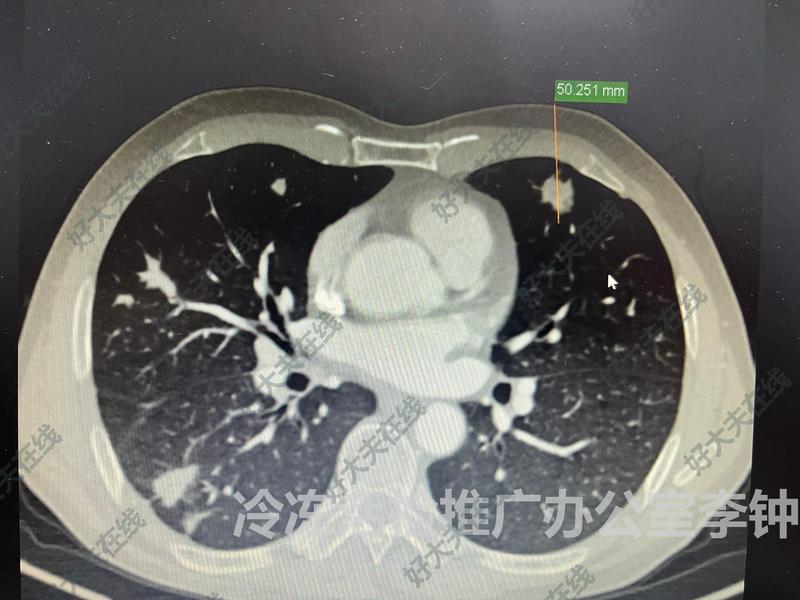

治療前雙肺多發(fā)肺結(jié)節(jié),petCT陽(yáng)性,考慮肺癌晚期,不想開胸活檢,也不想普通穿刺活檢擔(dān)心捅馬蜂窩。最后選擇局麻下冷凍活檢專利技術(shù)治療中在CT引導(dǎo)下,局麻下一個(gè)“小針眼”超微創(chuàng)專利針精準(zhǔn)穿刺入肺結(jié)節(jié)中心,建立密閉負(fù)壓通道,插入冷凍刀即刻對(duì)肺結(jié)節(jié)進(jìn)行三個(gè)循環(huán)的超低溫冷凍消融,復(fù)溫后拔出冷凍刀,用16G半自動(dòng)活檢槍對(duì)冷凍消融后的病灶在密閉負(fù)壓狀態(tài)進(jìn)行360度活檢,獲取大量組織標(biāo)本與組織液標(biāo)本。病人全程很安靜,沒(méi)有疼痛、沒(méi)有咯血、沒(méi)有血胸與血腫、少量氣胸。手術(shù)歷時(shí)2小時(shí),結(jié)束后自己下床安全返回病房。病人與家屬都非常高興!治療后治療后7天組織石蠟病理診斷是侵襲性肺腺癌,復(fù)查CT消融帶完全覆蓋肺結(jié)節(jié),達(dá)到局部根治的效果。